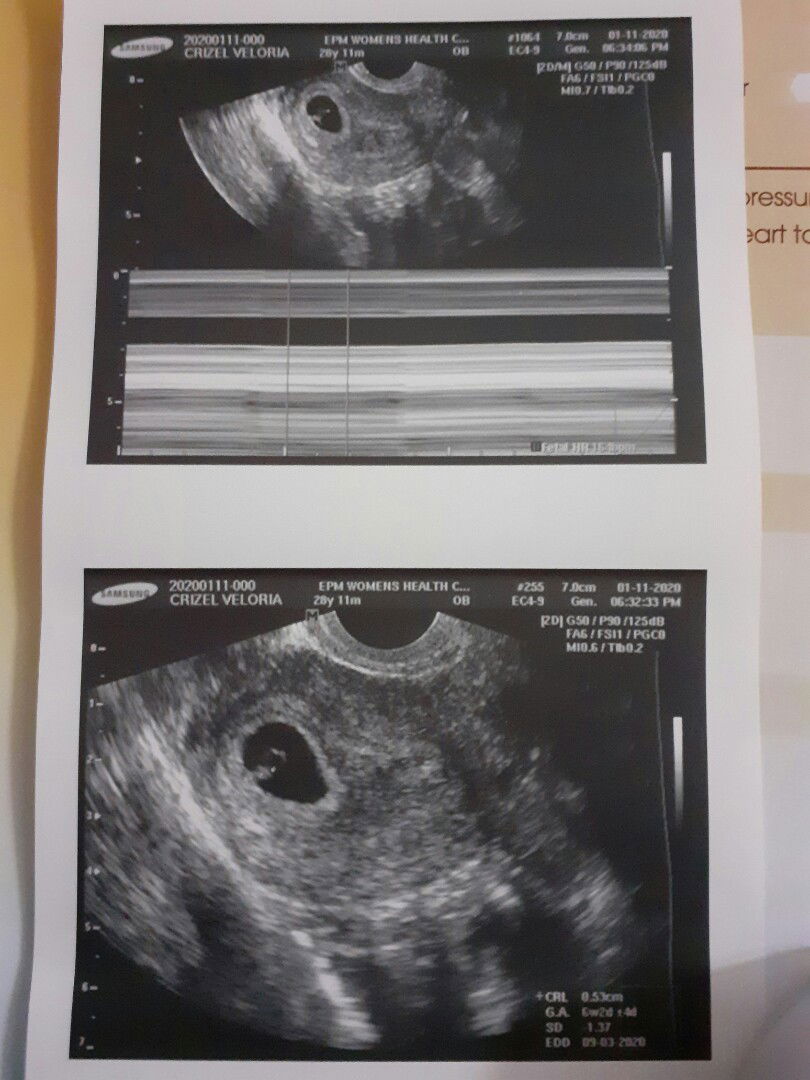

Good pm po, ask ko lang po kung naresetahan po ba kayo ng duphaston twice a day. Dahil daw nasa may bandang gitna si baby wala pa siya dun sa bandang taas. Dati kasi sa unang check up ko dahil sa palaging sumasakit ang puson at balakang ko niresetehan niya nko ng duphaston 3 times a day, ngayon twice a day na lang. Normal lang po kaya yun? Salamat po sa mag cocomment po :) God bless

Preggers